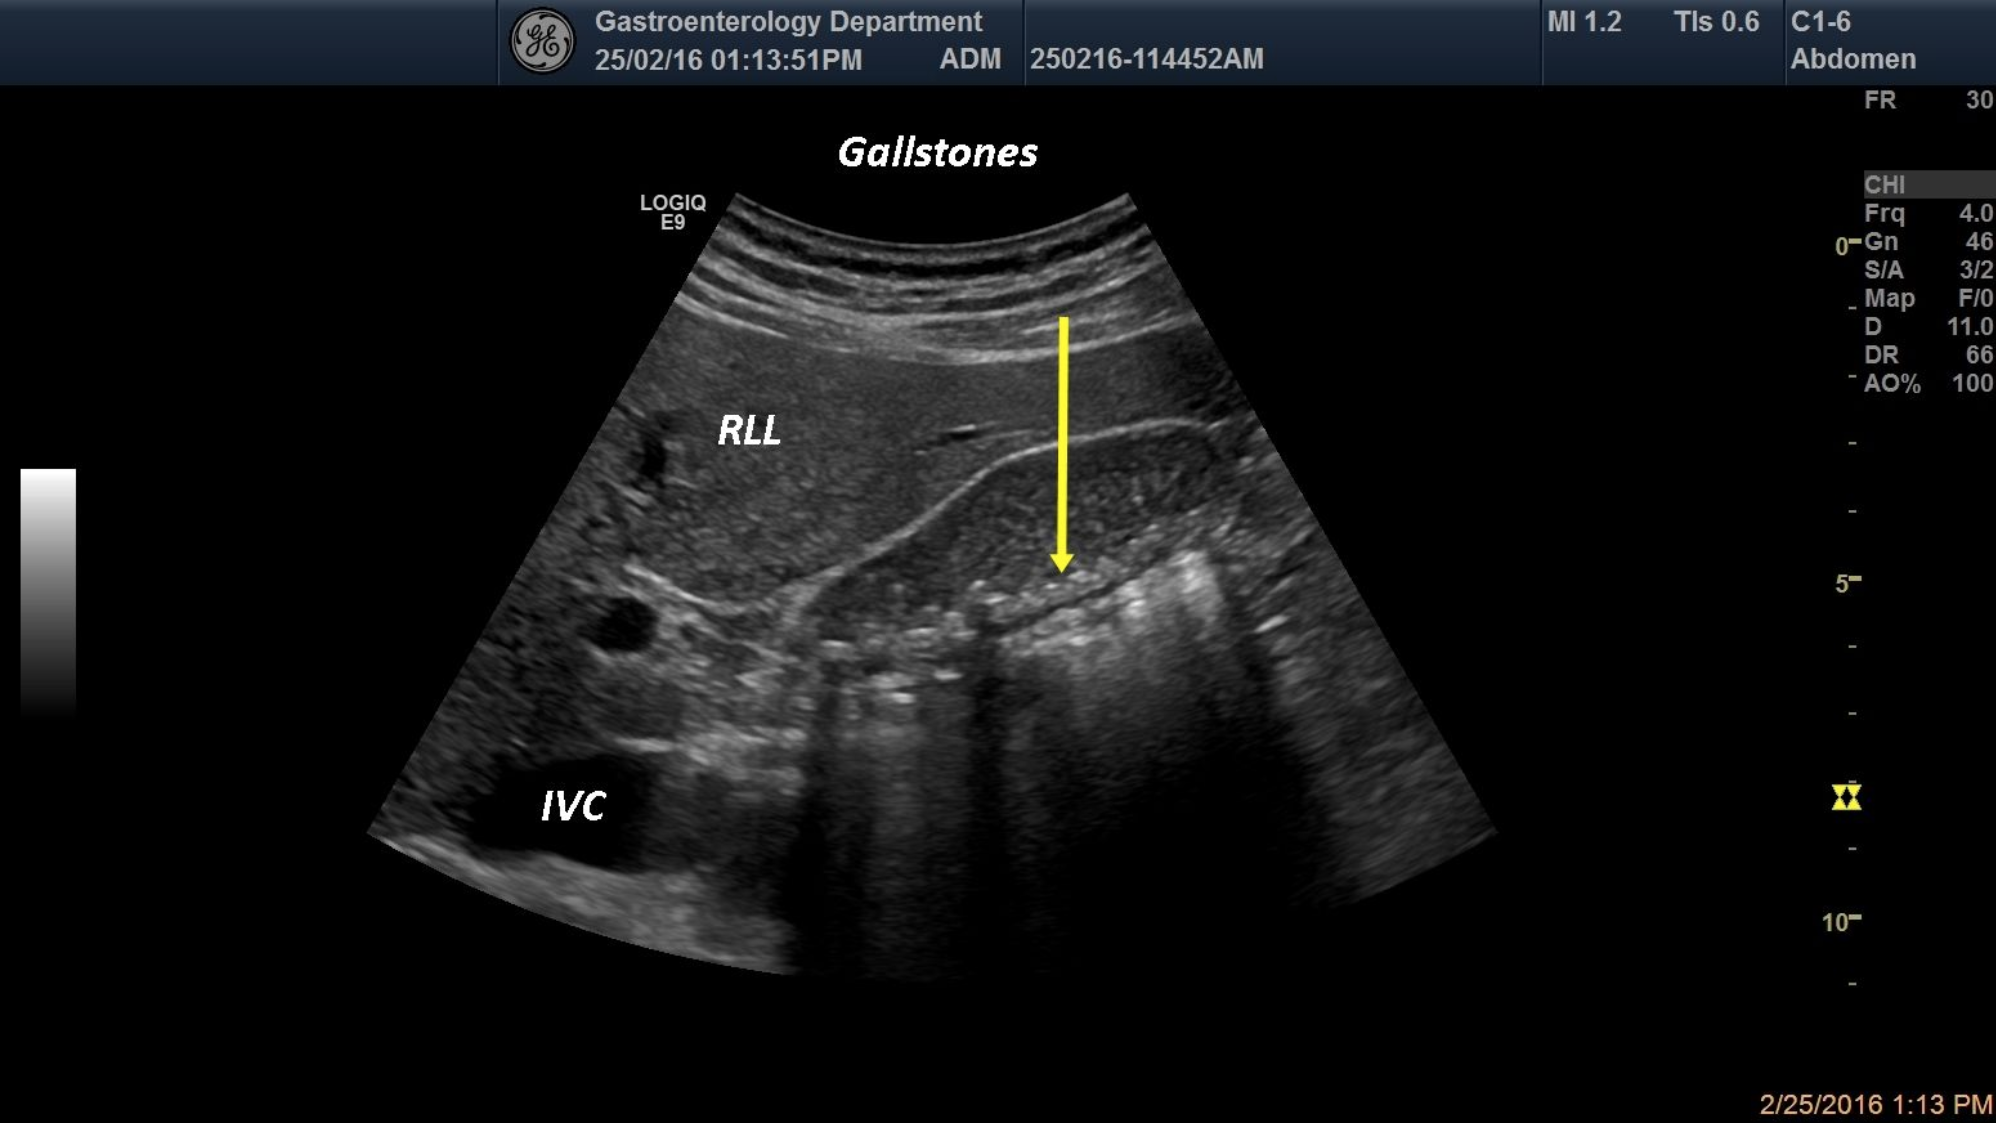

A-58-year old patient with multiple colicky pain was referred for a standard ultrasound. In the displayed image, multiple hyperechoic structures with posterior shadowing (gallstones) and biliary sludge are shown.

gallbladder, gallstones, biliary sludge